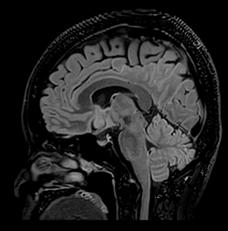

In particular DLR has an important clinical impact in anatomical regions that require a very high resolution, for example parts of the hippocampus and the claustrum.

“The DLR brings a spatial resolution that I have never seen before in neurologic imaging. I recently pointed out a brain area, for example the claustrum, that is almost invisible on standard MRI images even with very high resolution or high field devices. However, thanks

to the DLR we could highlight this kind of brain anatomy. So, indeed, there is a considerable advantage to using this technique.” Prof. Dousset said.

Prof. Tourdias worked at 7T to visualise extremely fine structures of the hippocampus while at Stanford. With DLR, he can now do this task with a 3T. “When we compared the images we realized that by pushing the 3T machine and processing with DLR that we were able to achieve a similar result to what we could achieve with 7T. I think this is the main surprise of the technology.” he said.